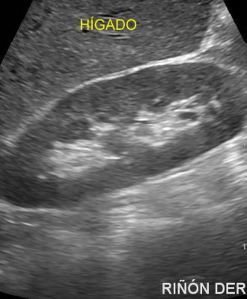

Otro estudio por ecografía muy útil es el Doppler de arterias renales, sobretodo cuando se sospecha de Hipertensión Renovascular debida a una Estenosis de Arteria Renal, en pacientes que inexplicablemente presentan elevación de la Presión Arterial, sostenida, o de difícil manejo. El doppler puede darnos una sensibilidad moderada pero el estudio ideal es la Arteriografía (Angiografía) o la Angiorresonancia.

En síntesis, el estudio ecográfico es muy útil en la aproximación diagnóstica en un paciente, pero al ser un estudio basado en ondas de sonido, no describe imágenes reales sino los «ecos» que éstas producen al ser expuestas al traductor del sonógrafo. Depende también además, del observador, es decir, del médico que realiza el examen pues pueden variar entre diferentes observadores. De todas maneras recomendamos que la ecografía o ultrasonografía sea realizada por un medico con especialidad hospitalaria de Radiología.